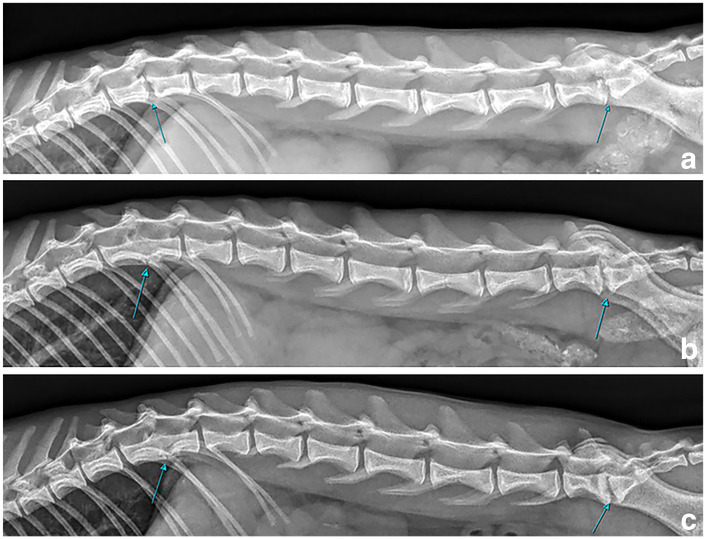

Case summary: A 1-year-old male castrated Savannah cat presented with chronic recurrent lethargy, stiffness, right pelvic limb lameness and spinal hyperaesthesia. Eight months before referral, the cat was treated with prednisolone, remdesivir and a 1-week course of amoxicillin/clavulanic acid and marbofloxacin for suspected feline infectious peritonitis. Multiple recurrences were reported after initial presentation, and were treated with 1-week courses of amoxicillin/clavulanic acid. Neurological examination did not reveal further findings. Haematology showed neutrophilia/monocytosis. Spinal, limb and thoracic radiographs revealed irregular endplates and narrowing of T12-T13 and L7-S1 intervertebral disc spaces, metaphyseal lesions of multiple long bones with heterogeneous medullary bone and reduced corticomedullary distinction, and two areas of increased opacity in the left lung lobes. Feline leukaemia virus, feline immunodeficiency virus, toxoplasma serology and urine culture were negative. Blood culture was positive for Salmonella species. Amoxicillin/clavulanic acid (20 mg/kg q12h) was started with clinical improvement, but no resolution of haematological/imaging changes. Relapse occurred 7 months into treatment. Blood culture showed Phocaeicola massiliensis, a suspected contaminant. Metronidazole (11 mg/kg q12h) was added based on sensitivity, with clinical improvement but relapse after discontinuation 4 months later. Neutrophilia and monocytosis were again identified, alongside hyperproteinaemia and globulinaemia. Recheck radiographs showed a worsening of the osteomyelitis but an improvement of the discospondylitis. Salmonella species were cultured again from blood and bone biopsies. Marbofloxacin (4.5 mg/kg q24h) was initiated. At the 6-month follow-up, complete resolution of clinical and laboratory findings was documented alongside radiographic improvement of the previous lesions. Treatment was discontinued with no relapses over the 10-month follow-up.